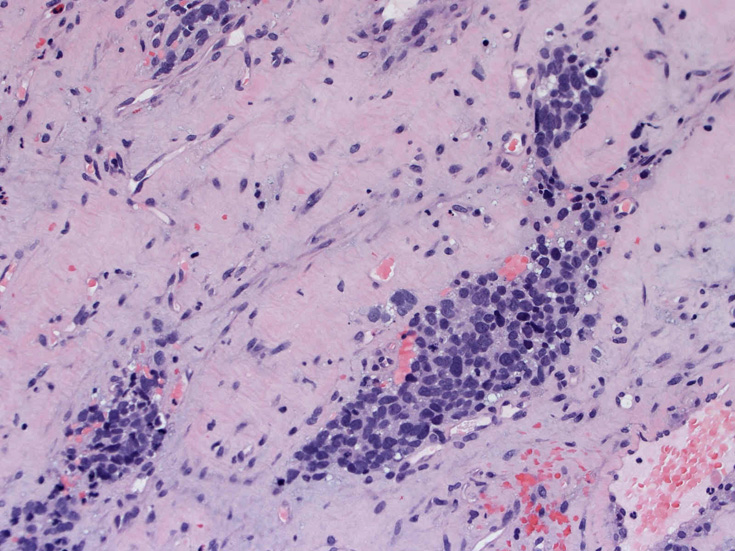

30歳代男性 鼻腔腫瘤の生検組織

厳密にはalveolar patternが明らかではなく, solid typeに入る症例かもしれない。異型細胞増殖胞巣が線維化組織に取り囲まれるように散在している. 小さな生検組織のため全体像が不明である。